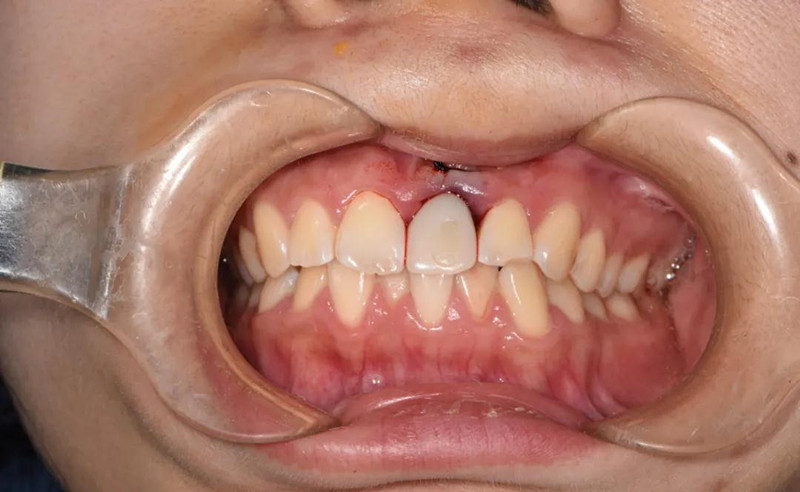

患者术前口内像

即刻修复后患者自然开口下面像

即刻修复后唇侧口内像

术后2周后唇侧口内像